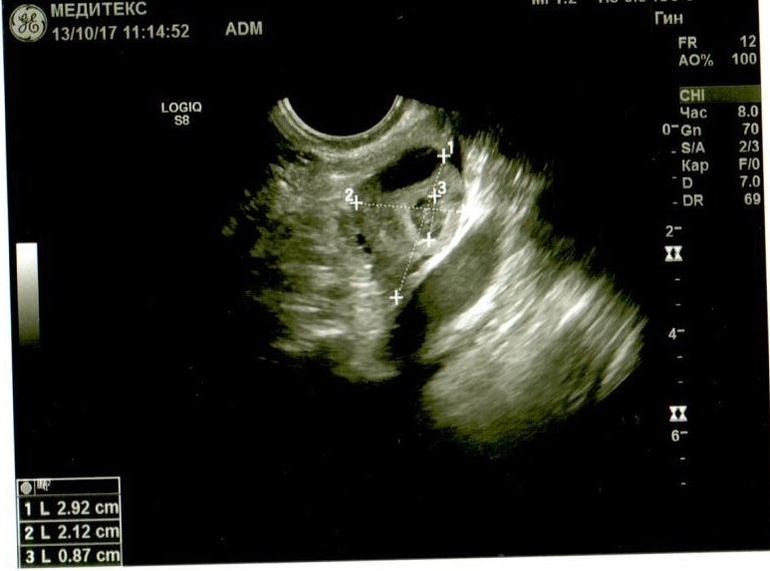

Если можно, посмотрите. Буду очень благодарна. Не очень в этом разбираюсь, поэтому выкладываю все снимки и заключение узистки.

Добрый день! У Вас в самой структуре яичника имеются гиперэхогенные включения, которые говорят о перенесенном воспалении, при этом о спайках может говорить только расположение яичников возле матки ( это если опираться на описание, так как на фото не видно). Однозначно, имеет место хронический оофорит. И в эндометрии мне не нравится зона в области дна. Врач ее даже выделила, но не описала. Эндометрий неоднородный, стоит сделать УЗИ на 5 день цикла повторно.